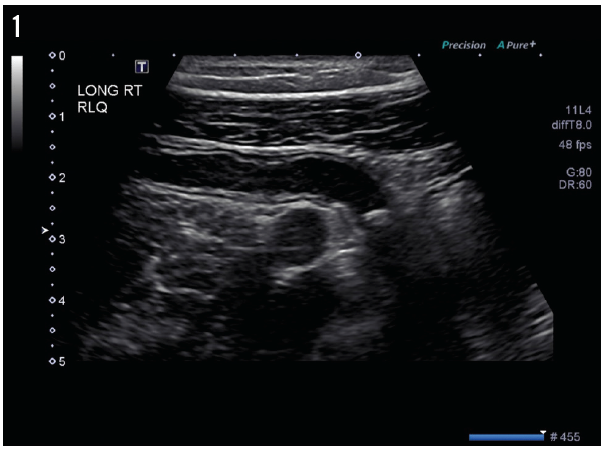

On day 5 of hospitalization, the patient still complained of lower abdominal pain despite opioid analgesics, prompting further ultrasonography scans, the results of which are shown in Figures 1 and 2.

The results of pelvic ultrasonography (Figure 1) showed an elongate, tubular, noncompressible bowel loop in the right lower quadrant, measuring 8 mm, likely representing the appendix with a blind end, and suggesting acute appendicitis with appendicolith but without evidence of perforation. A cross-sectional scan (Figure 2) showed no free fluid or periappendicular fluid collection that would suggest perforation; it also demonstrated the “ring of fire” due to the high vascularity of the inflamed appendix (Figure 3).

Figure 2. A cross-sectional ultrasonography scan showed a shadowing calculus, likely representing appendicitis with appendicolith. No obvious free fluid or periappendicular fluid collection is visible to suggest perforation.